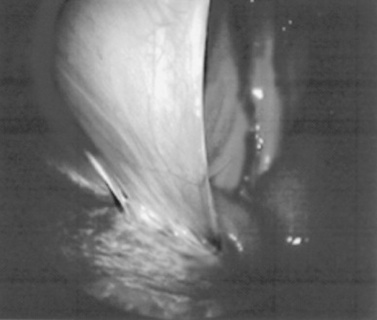

Systematic examination of the abdominal cavity is then carried out. On the left side of the abdomen the spleen, left kidney, nephrosplenic ligament (Fig. 32-1), stomach, left side of liver, diaphragm, and ventral colon may be visualized cranially. Looking caudally, the examiner will see the root of the mesentery, the isolated small intestinal and small and large colon sections, the urogenital tract, the bladder, and the terminal rectum. The procedure is repeated on the right side of the abdomen. Looking cranially, the examiner will see the liver, epiploic foramen, right kidney, descending duodenum, cecal base, and large colon. Caudally, the urogenital tract, root of mesentery, and isolated pieces of intestine are visible. Liver biopsies and right kidney biopsies are taken from the right side. Left kidney and spleen biopsies are taken from the left side of the abdomen. Mesenteric lymph node biopsies are usually obtained via the left flank. Other masses are biopsied from the more accessible side. At the end of the procedure the abdomen is deflated, and the skin is closed with skin sutures only. Closure of the skin incision should wait until examination of both sides is completed in order to minimize subcutaneous emphysema.

image

Fig. 32-1 Laparoscopic view of nephrosplenic ligament in a horse.